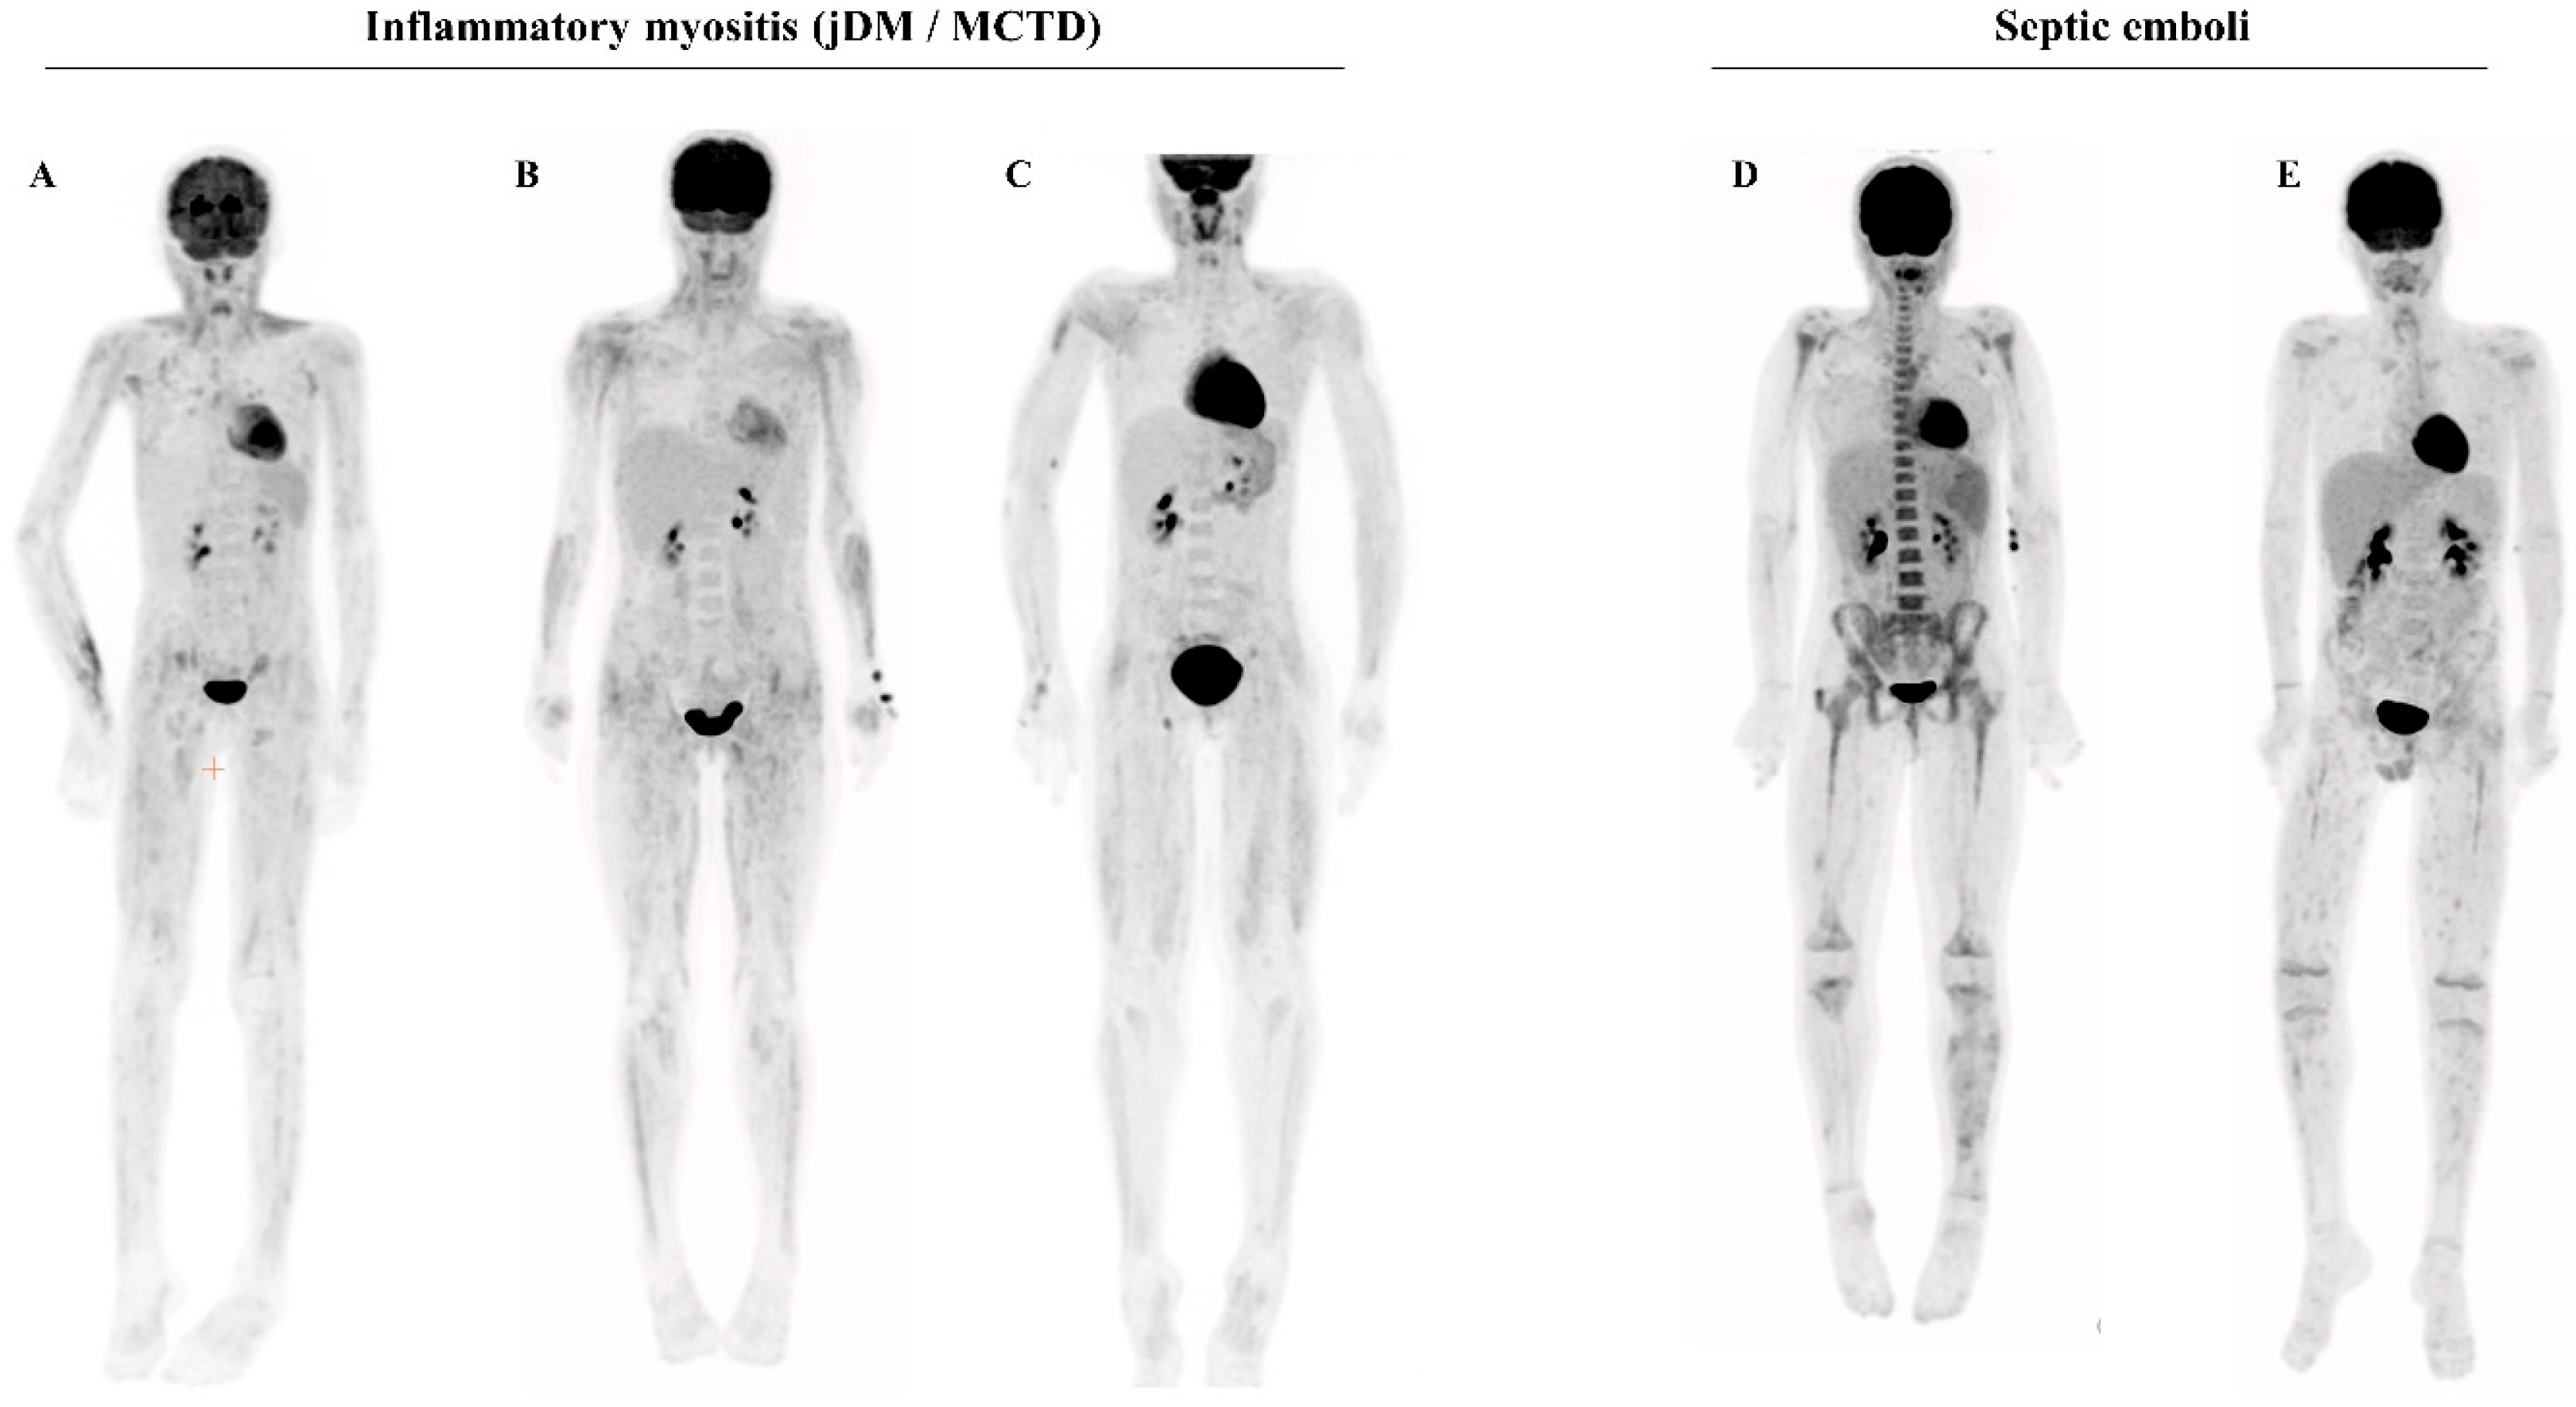

3.4. PET-CT Findings in Other Conditions

To assess whether the muscular and cutaneous/subcutaneous heterogeneous FDG uptake could be differentiated from muscle inflammation found in other conditions, we searched the local CHUSJ PET-CT database. We compared the PET-CT of PAN patients with that of patients with other inflammatory myositis (n = 7) (idiopathic dermatomyositis or myositis of mixed connective tissue disorder), or septic muscular emboli (n = 2). The PET-CT of inflammatory myositis displayed the following differences: (i) an absence of cutaneous/subcutaneous FDG uptake; (ii) a more proximal and homogeneous, linear distribution of the muscular FDG uptake (Figure 3A–C). The muscular PET-CT findings in the patients with septic emboli displayed no robust difference from PAN (Figure 3D–E).

Figure 3. (AC) Illustrative examples of PET-CT findings in juvenile dermatomyositis (jDM) or mixed connective tissue disorders (MCTD): symmetrical, diffuse, linear increased muscular uptake affecting the limbs, more marked proximally than distally. No cutaneous/subcutaneous lesions. Anti-MDA5 in (A), anti-Ro52 in (B), and anti-SRP in (C). (D,E) Illustrative examples of PET-CT findings in patients with septic emboli (Staphylococcus Aureus bacteremia in the context of bacterial endocarditis in (D), during a stem cell transplantation for leukemia in (E)). Non-symmetrical random regions of uptake in soft tissues of the lower extremities (arrows), including the right greater trochanter bursa in patient (D) (arrowhead).